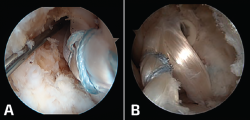

En los últimos años se han desarrollado un gran número de técnicas de reconstrucción ligamentosa por vía artroscópica(7,8,9,10,11,12,13,14,15,16,17,18,19,20) para la reconstrucción del LTFA (Figura 5A) y el LCF (Figura 5B). Conviene recordar una vez más el doble papel de la reconstrucción del complejo lateral, tanto en un intento de prevenir o frenar la evolución de la artrosis de tobillo (estadio I) como un gesto asociado a la cirugía de preservación articular (estadio II).

Figura 5. A: reconstrucción artroscópica con aloinjerto del ligamento talofibular anterior (LTFA); B: reconstrucción artroscópica con aloinjerto del LTFA y ligamento calcáneo fibular.